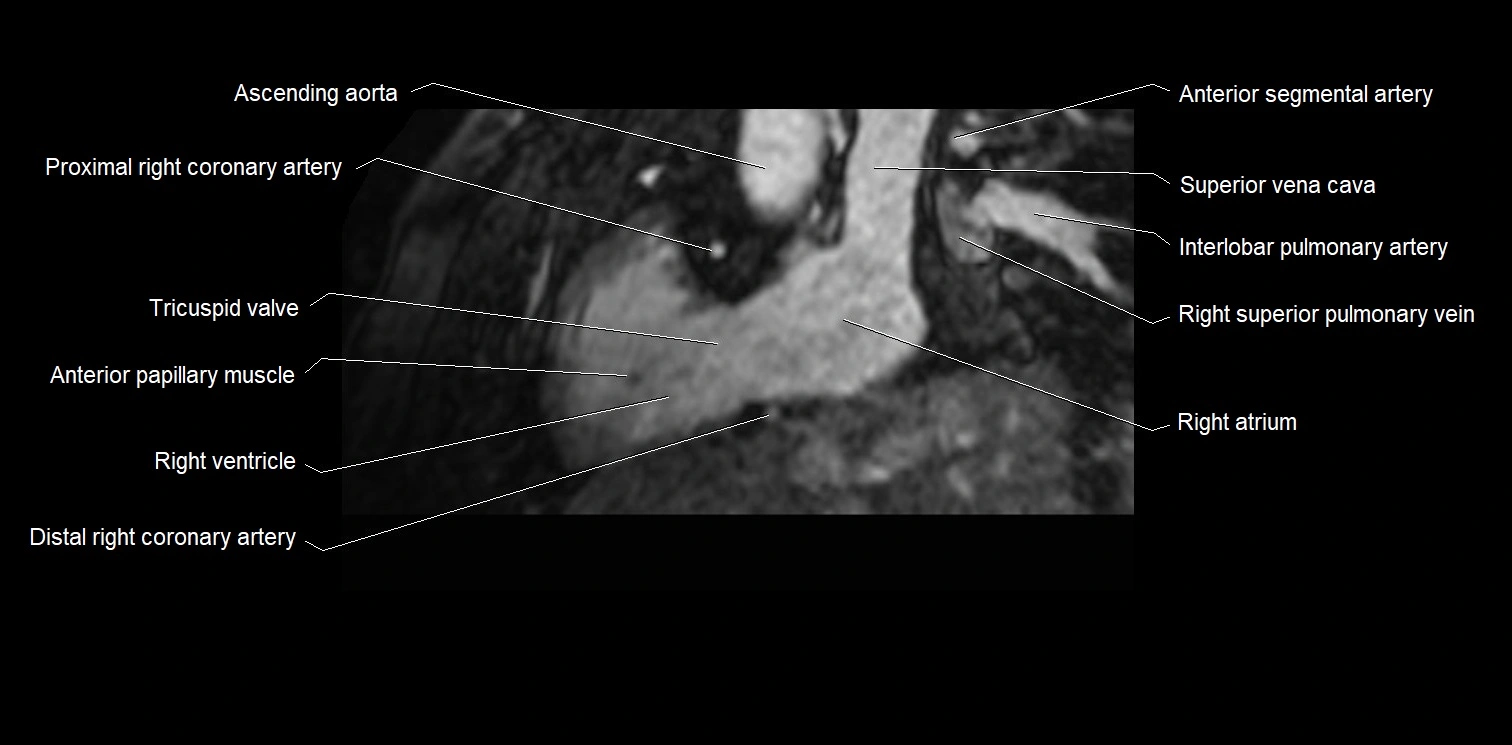

MRI image